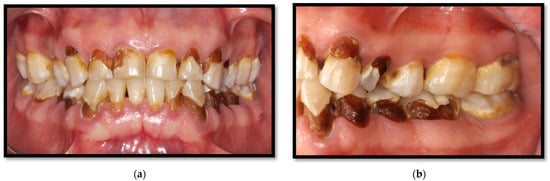

11. Caries